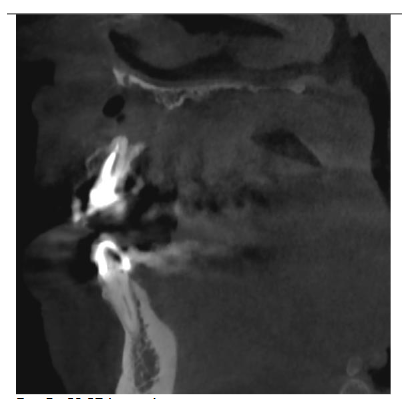

CBCT lateral scan

Radiographic examination revealed necrosis around the apex of tooth 12, with CBCT scans showing damage to both the buccal and palatal cortical plates. A decision was made for one-step treatment, and anticoagulant therapy was not interrupted.

CBCT horizontal. Visible damage of buccal and palatal plate